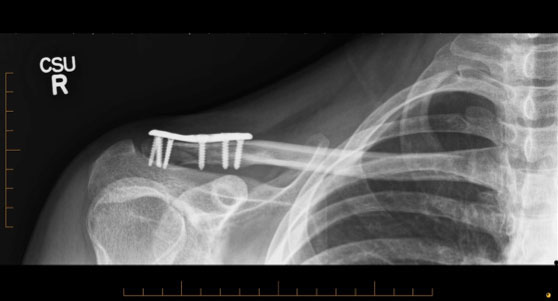

In considerable pain and with a noticeable lump on his collarbone and a “floppy” arm, Chris was taken to the nearest emergency department where x-rays confirmed a displaced fracture on the distal (outer) end of his collarbone.

“As these types of fractures have a high chance of not healing, I chose to operate soon after seeing Chris to reduce and realign the fracture with a new surgical plate especially designed to treat these types of fractures,” Dr Duckworth said.

Collarbone realigned with a new custom designed plate

The new plate is smaller than other plates commonly used and has more options to screw the plate to the bone, which provides surgeons with greater precision in positioning the plate and stabilising the fracture, he said.